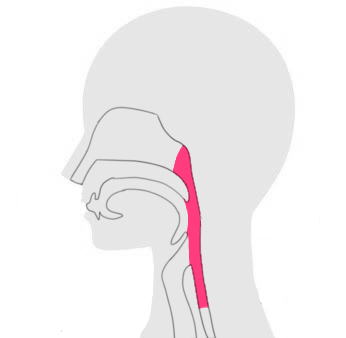

喉頭がんの「初期症状や、原因、治療方法など」は以下からご参考ください。

喉頭がんだけに限らず、がん治療にて根治を目指す場合、重要となってくるのは、早期段階による治療です。

がんのステージに関係なく行える治療方法であり、喉頭がんが含めおおよそ全身の癌に対応することが可能です。